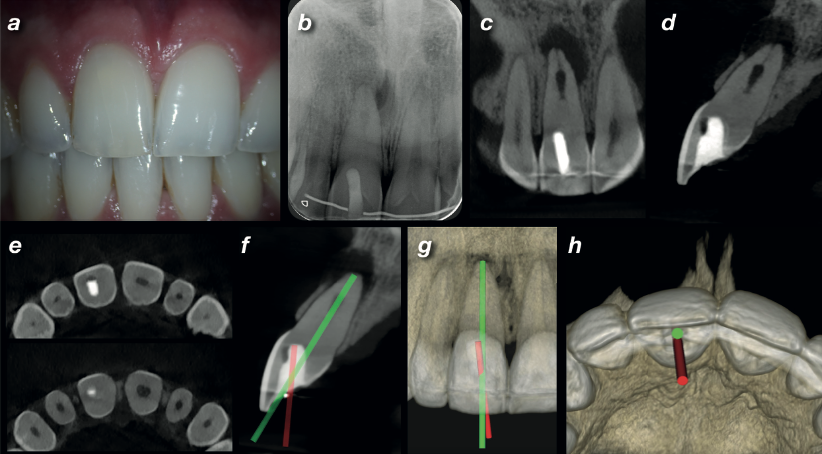

Clinical photo, periapical radiograph, and CBCT coronal, sagittal, and axial views of UR1 showing deviated access, calcified canal, internal resorption, and periapical radiolucency with virtual endodontic guide overlay

Fig. 1 (a) Clinical photo showing slight discolouration of UR1. (b) Periapical radiograph revealing deviated access, calcified canal, internal resorption, and periapical radiolucency. (c–d) CBCT coronal and sagittal planes. (e) Axial view showing the off-angle access. (f–h) Virtual endodontic guide comparing the correct drilling path (green) with the original failed access (red).

A 26-year-old male was referred after his dentist was unable to locate the root canal in the upper right central incisor (UR1) during endodontic treatment. The tooth was tender to palpation and percussion, with slight discolouration compared to the opposite side — a classic sign of pulp canal obliteration following earlier trauma.

The periapical radiograph told a worrying story: a deviated access cavity from the first attempt, a calcified root canal, internal resorption, and a periapical radiolucency. The initial treatment had gone off course — the access was angled in the wrong direction, and the canal had never been located.

A high-resolution CBCT scan was taken using the Carestream CS 8100 3D with a limited 5×5 cm field of view at 75-micron voxel size. The scan clearly showed the deviation of the initial access, the extent of the calcification, the internal resorption, and the periapical lesion with perforation of the buccal cortical plate.

Using the CBCT data, a "virtual endodontic guide" was designed — overlaying the correct drilling path onto the scan alongside the failed original access. The difference was immediately visible: the first attempt had been angled too far in one direction to ever reach the canal.